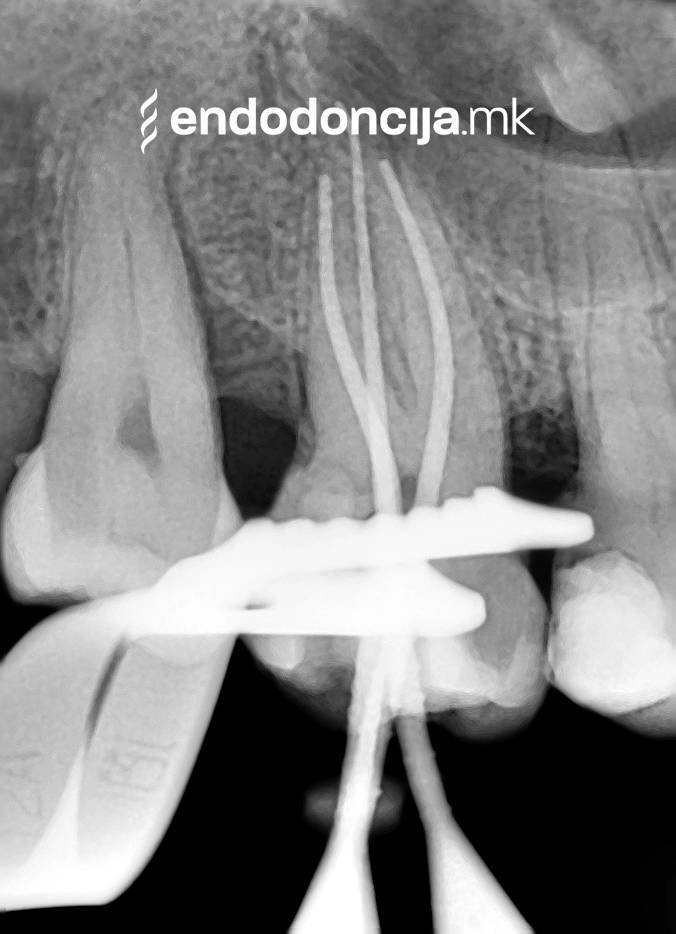

Εκτός από την ανίχνευση των ριζικών καναλιών, η ενδελεχής προετοιμασία και η απολύμανση του ριζικού σωλήνα είναι η προϋπόθεση για μια επιτυχημένη συνολική θεραπεία. Μέσω της χρήσης των νεότερων οργάνων και αντιβακτηριακών διαλυμάτων, όλα τα υπολείμματα ιστών και τα βακτήρια που υπάρχουν μπορούν να εξαλειφθούν.

Κατά τη διάρκεια της επεξεργασίας του ριζικού σωλήνα, τα λεπτά όργανα ενδέχεται να σπάσουν. Αυτό μπορεί να αποτελέσει εμπόδιο για την πλήρη προετοιμασία και τον καθαρισμό του ριζικού σωλήνα. Με μια μικροσκοπική επεξεργασία του ριζικού σωλήνα μπορεί να είναι δυνατή η απομάκρυνσή τους υπό ορισμένες συνθήκες, χωρίς να καταστρέφεται η ουσία των δοντιών.